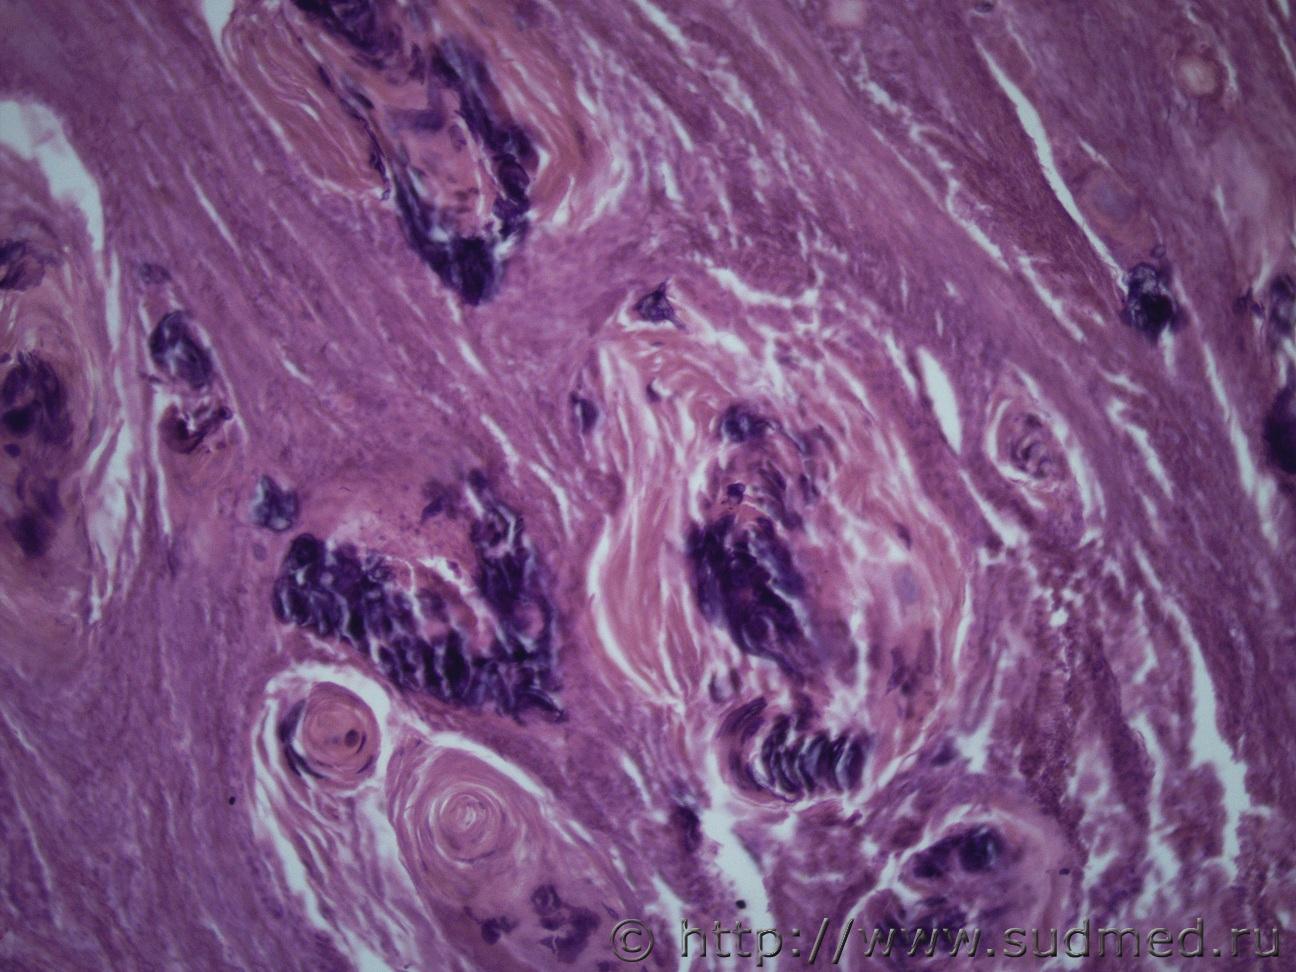

И еще одна опухоль матки жен 1969 г.рСудебная медицина - Прикрепленное изображение Судебная медицина - Прикрепленное изображениеСудебная медицина - Прикрепленное изображениеСудебная медицина - Прикрепленное изображениеСудебная медицина - Прикрепленное изображение

Плоскоклеточный умереннодифференцированный рак,инвазия в железы.

Согласен! Наблюдается ороговение в виде жемчужин.